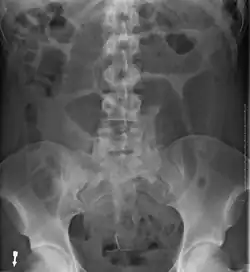

- Abdominal x-ray – tire-like shadow arising from the right iliac fossa and passing to the left

- Plain X ray of a cecal volvulus